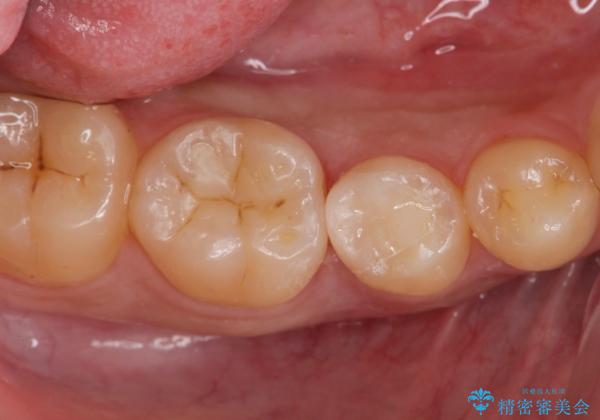

古い樹脂を除去してe-maxインレー

拡大鏡下で古い樹脂を除去し、虫歯がない事を確認してe-maxインレーで治療を行いました。

適合の良い詰め物が入りました。

セラミックは虫歯の再発のリスクが少ないです。